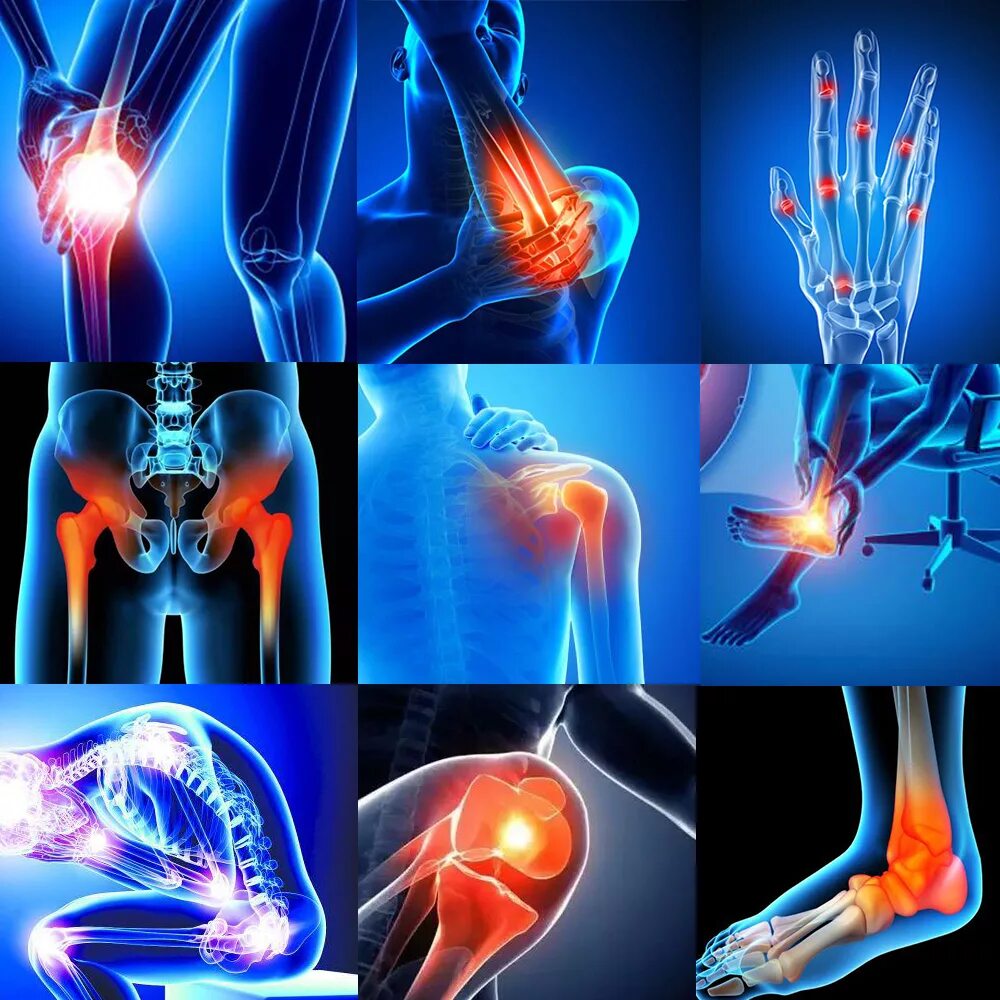

Ревматизм ног